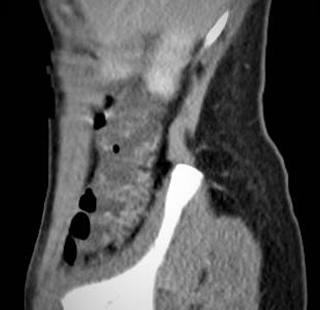

La angiotomografia informó alteraciones de las estructuras vasculares, observándose imágenes compatibles con várices que comprometen el colon derecho y se extienden hasta el recto. También se observa marcado compromiso del íleon terminal y cambios del grosor de las ramas de los vasos mesentéricos, algunos dilatados, comprometiendo especialmente las venas mesentéricas superior e inferior. No se visualizan zonas estenóticas en el colon ni en intestino delgado. Recto y grasa regional sin alteraciones. Si bien se observa un aumento de la vasculatura a dicho nivel, es menor que la descripta y visualizada principalmente en el colon derecho e íleon terminal. Calibre de la vena porta 12mm y de la vena esplénica 4mm. No se observó trombosis venosa (Fig. 2 A y B).

B A

Figura 2. Angiotomografía computarizada. A. Corte coronal. Várices colónicas y engrosamiento y dilatación de ramas de las venas mesentérica superior e inferior. B. Corte sagital. Varices colónicas.